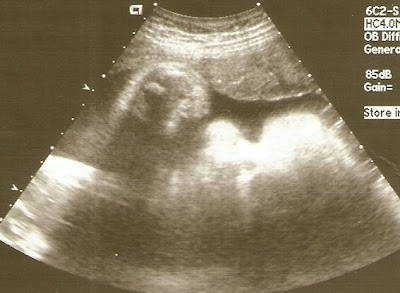

Here are two pictures from today's F.A. They're both a nose & lips shot. Look at those lips!

The doctor at fetal assessment was actually quite happy with the results of the fetal assessment. They baby's still big (almost 8 lbs now), but she's steady at the 90th percentile - not still rising, so that's good. Everything else about her looks great - heart, lungs, liver, kidneys, brain, etc. She's not showing any signs of problems. In fact, her responsiveness to touch (she kicked the ultrasound machine numerous times), and the practice-breathing she's doing are very good signs of both physical and mental developement, so that's good to hear. We even saw her make sucking motions with her mouth! So there's definitely no cause for immediate concern, but we/they definitely want to keep an eye on her.